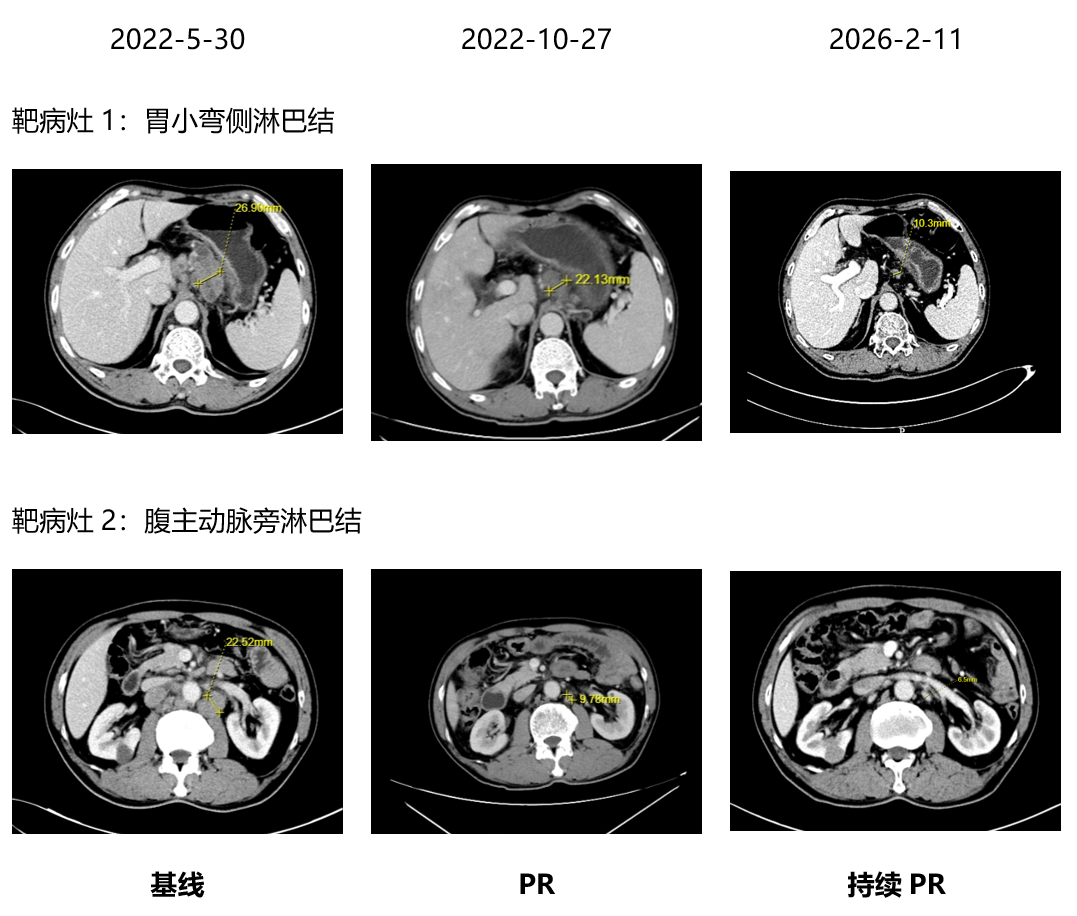

于2022-06-13入组,2022-6-27至2026-2-12行第C1-C63治疗,具体用药:ZW25 1800mg+替雷利珠单抗200mg d1+奥沙利铂 130mg/m2 d1+卡培他滨 1000/750/500mg/m2 bid po d1~14, Q3W。(C7起停用奥沙利铂,因甲沟炎下调卡培他滨剂量)。

影像学评估:部分缓解(PR)

目前仍在组治疗中,一线PFS已超过44个月。

本文分享的患者为PD-L1低表达(CPS=1)、初治时已属IV期伴远处转移,属于传统治疗预后不佳的人群。然而,在加入HERIZON-GEA-01研究后,患者快速缩瘤,虽然从2023年起CEA水平有所升高并超出正常参考值上限,但其后的多次影像学复查(直至最近一次2026年2月)均保持PR状态,未见明确进展征象,已获得了超过44个月的超长PFS。这强有力地印证了临床研究数据,表明“泽尼达妥单抗+替雷利珠单抗+化疗”方案能够诱发深度且持久的治疗应答,甚至让部分晚期患者获得类似慢性病管理的长周期生存效益,这是肿瘤治疗追求的重要目标。